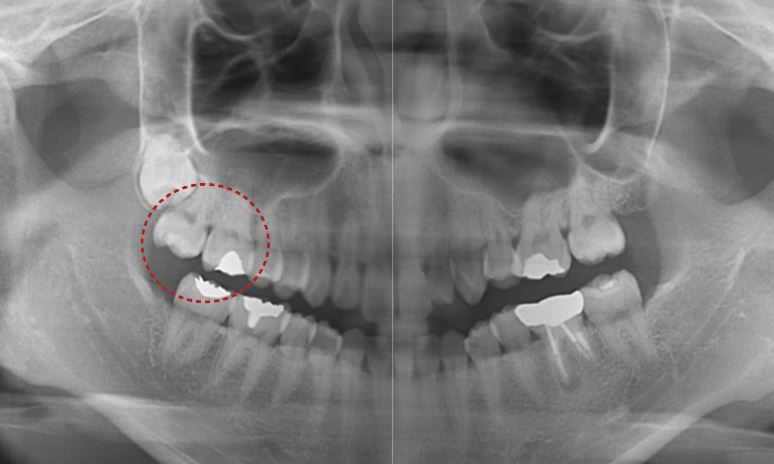

Problem List

상악 중절치 사이 및 왼쪽 송곳니 후방 spacing

상악 중철치 치축이 기울어져있습니다.

상악 왼쪽 측절치의 사이즈가 작습니다.(기형치)

상악 중절치가 정출되어 있습니다.

Problem List 확인 결과

상악의 중간 선과 하악의 중간선이 맞지 않고

기울어져 있는 걸 확인할 수 있어요-:D

그리고 상악 왼쪽에 있는 측절치의 사이즈가

평균 치아크기보다 조금 더 작더라고요.